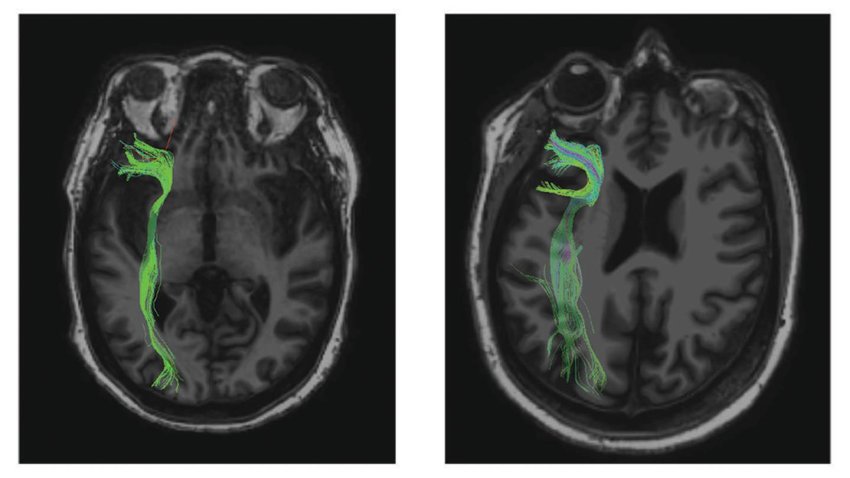

La fMRI a sinistra mostra un cervello invecchiato con connessioni compromesse, e quella a destra un cervello invecchiato con connessioni simili al cervello di soggetti test molto più giovani. (Fonte: Johns Hopkins University)

Le scansioni del cervello hanno dimostrato che in alcuni partecipanti che invecchiano, le fibre che collegano la parte anteriore e posteriore del cervello sembrano essersi danneggiate nel corso degli anni. Tuttavia, altri individui anziani avevano fibre simili a soggetti molto più giovani. Maggiore è l'integrità di queste fibre, migliore è l'esecuzione del compito del partecipante, ha affermato il primo autore Thomas Hinault, post dottorato della Johns Hopkins.